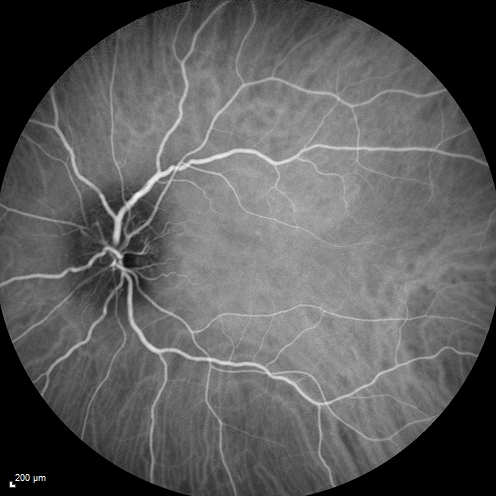

Syphillitic Optic Neuropathy and Maculopathy

46 year old woman with 2 weeks of vision loss OD.  VA 20/200 OD; 20/20 OS.  there are posterior vitreous cells on OCT in both eyes.  ICG, FAF, and FA show an abnormal macula OD.  VA improved to 20/30 within a month with treatment with PCN.